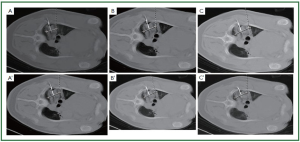

Experimental study

We evaluated (37) lung necrosis by CT-scan and histology in a porcine model using different freeze-thaw cycles during percutaneous cryosurgery under CT guidance. Three cryoprobes were inserted into both the left and right lung for each pig, respectively. For the left lung cryoablation was performed by two cycles of freezing with each 10 minutes followed by 5-minute thawing, while for the right lung, the cycles were the same as the left lung but with each 5-minute freezing and plus another (third) cycle of 10-minute freezing and 5-minute thawing. The cryolesional samples were taken at 4-hour, 3 and 7 days postoperatively. Our results showed the ice-ball grew gradually in relation to the increase in time and cycles. The size of the cryolesion became larger than the ice-ball during cryosurgery, regardless of 2 or 3 freeze-thaw cycles were performed. The area of necrosis gradually increased as time increased (Figures 4, 5, 6). It is suggested that three freeze-thaw cycles are necessary for the complete cryoablation of lung parenchyma, and “1-cm safe rim” may be not necessary during lung cryosurgery in order to avoid harming the organ and tissue close to the cancer.

Figure 4. The CT-imaging of pulmonary parenchyma after freezing and thawing. The ice-ball grew gradually in relation to the increase in time and cycles. A and A'. Five minutes after first cycle of freeze-thaw; B and B'. Five minutes after second cycle of freeze-thaw; C and C'. Five minutes after third cycle of freeze-thaw.